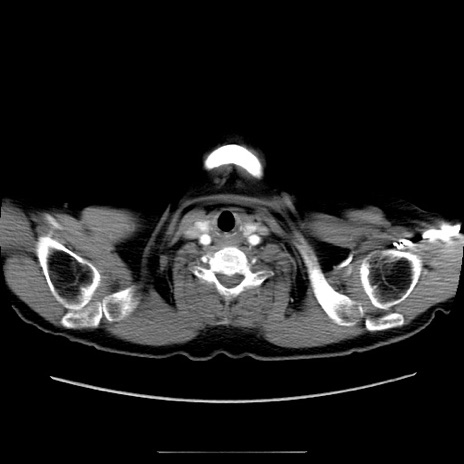

冠状断像

【症例】70歳代女性

【主訴】お腹が張る

【現病歴】1週間くらい前から腹部膨満の自覚あり。昨日夜から増悪したため、本日救急外来受診。

【身体所見】意識清明、BT 36.5℃、BP 165/106mmHg、HR 80bpm、SpO2 98%、腹部:膨満、軟、自発痛・圧痛なし、触診にて不快感あり、腸蠕動音:減弱

【データ】WBC 12600、CRP 1.04